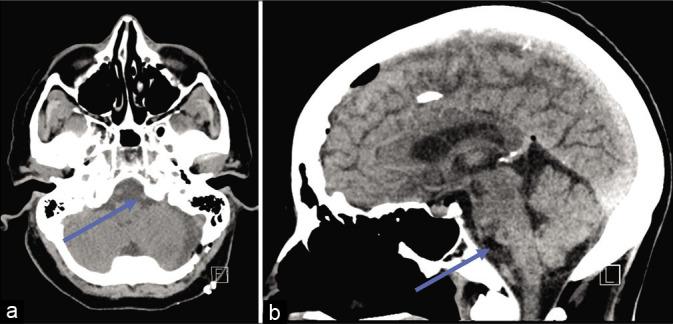

We present the case of a 75-year-old woman with an extra-axial cystic lesion centered in the premedullary cistern causing brainstem compression. The lesion was later histopathologically confirmed to be a neurenteric cyst. She presented initially with a 4-month history of worsening headache, dizziness, and unsteady gait. We performed a left retrosigmoid craniotomy for cyst fenestration/biopsy with the aid of operating microscope and stealth neuronavigation. Following the procedure, the patient recovered without complications or residual deficits.

This case illustrates the successful fenestration of an intracranial neurenteric cyst with good clinical outcome. We present the pre- and post-operative imaging findings, a technical video of the procedure, histopathological confirmation, and a brief review of the relevant clinical literature on the topic.